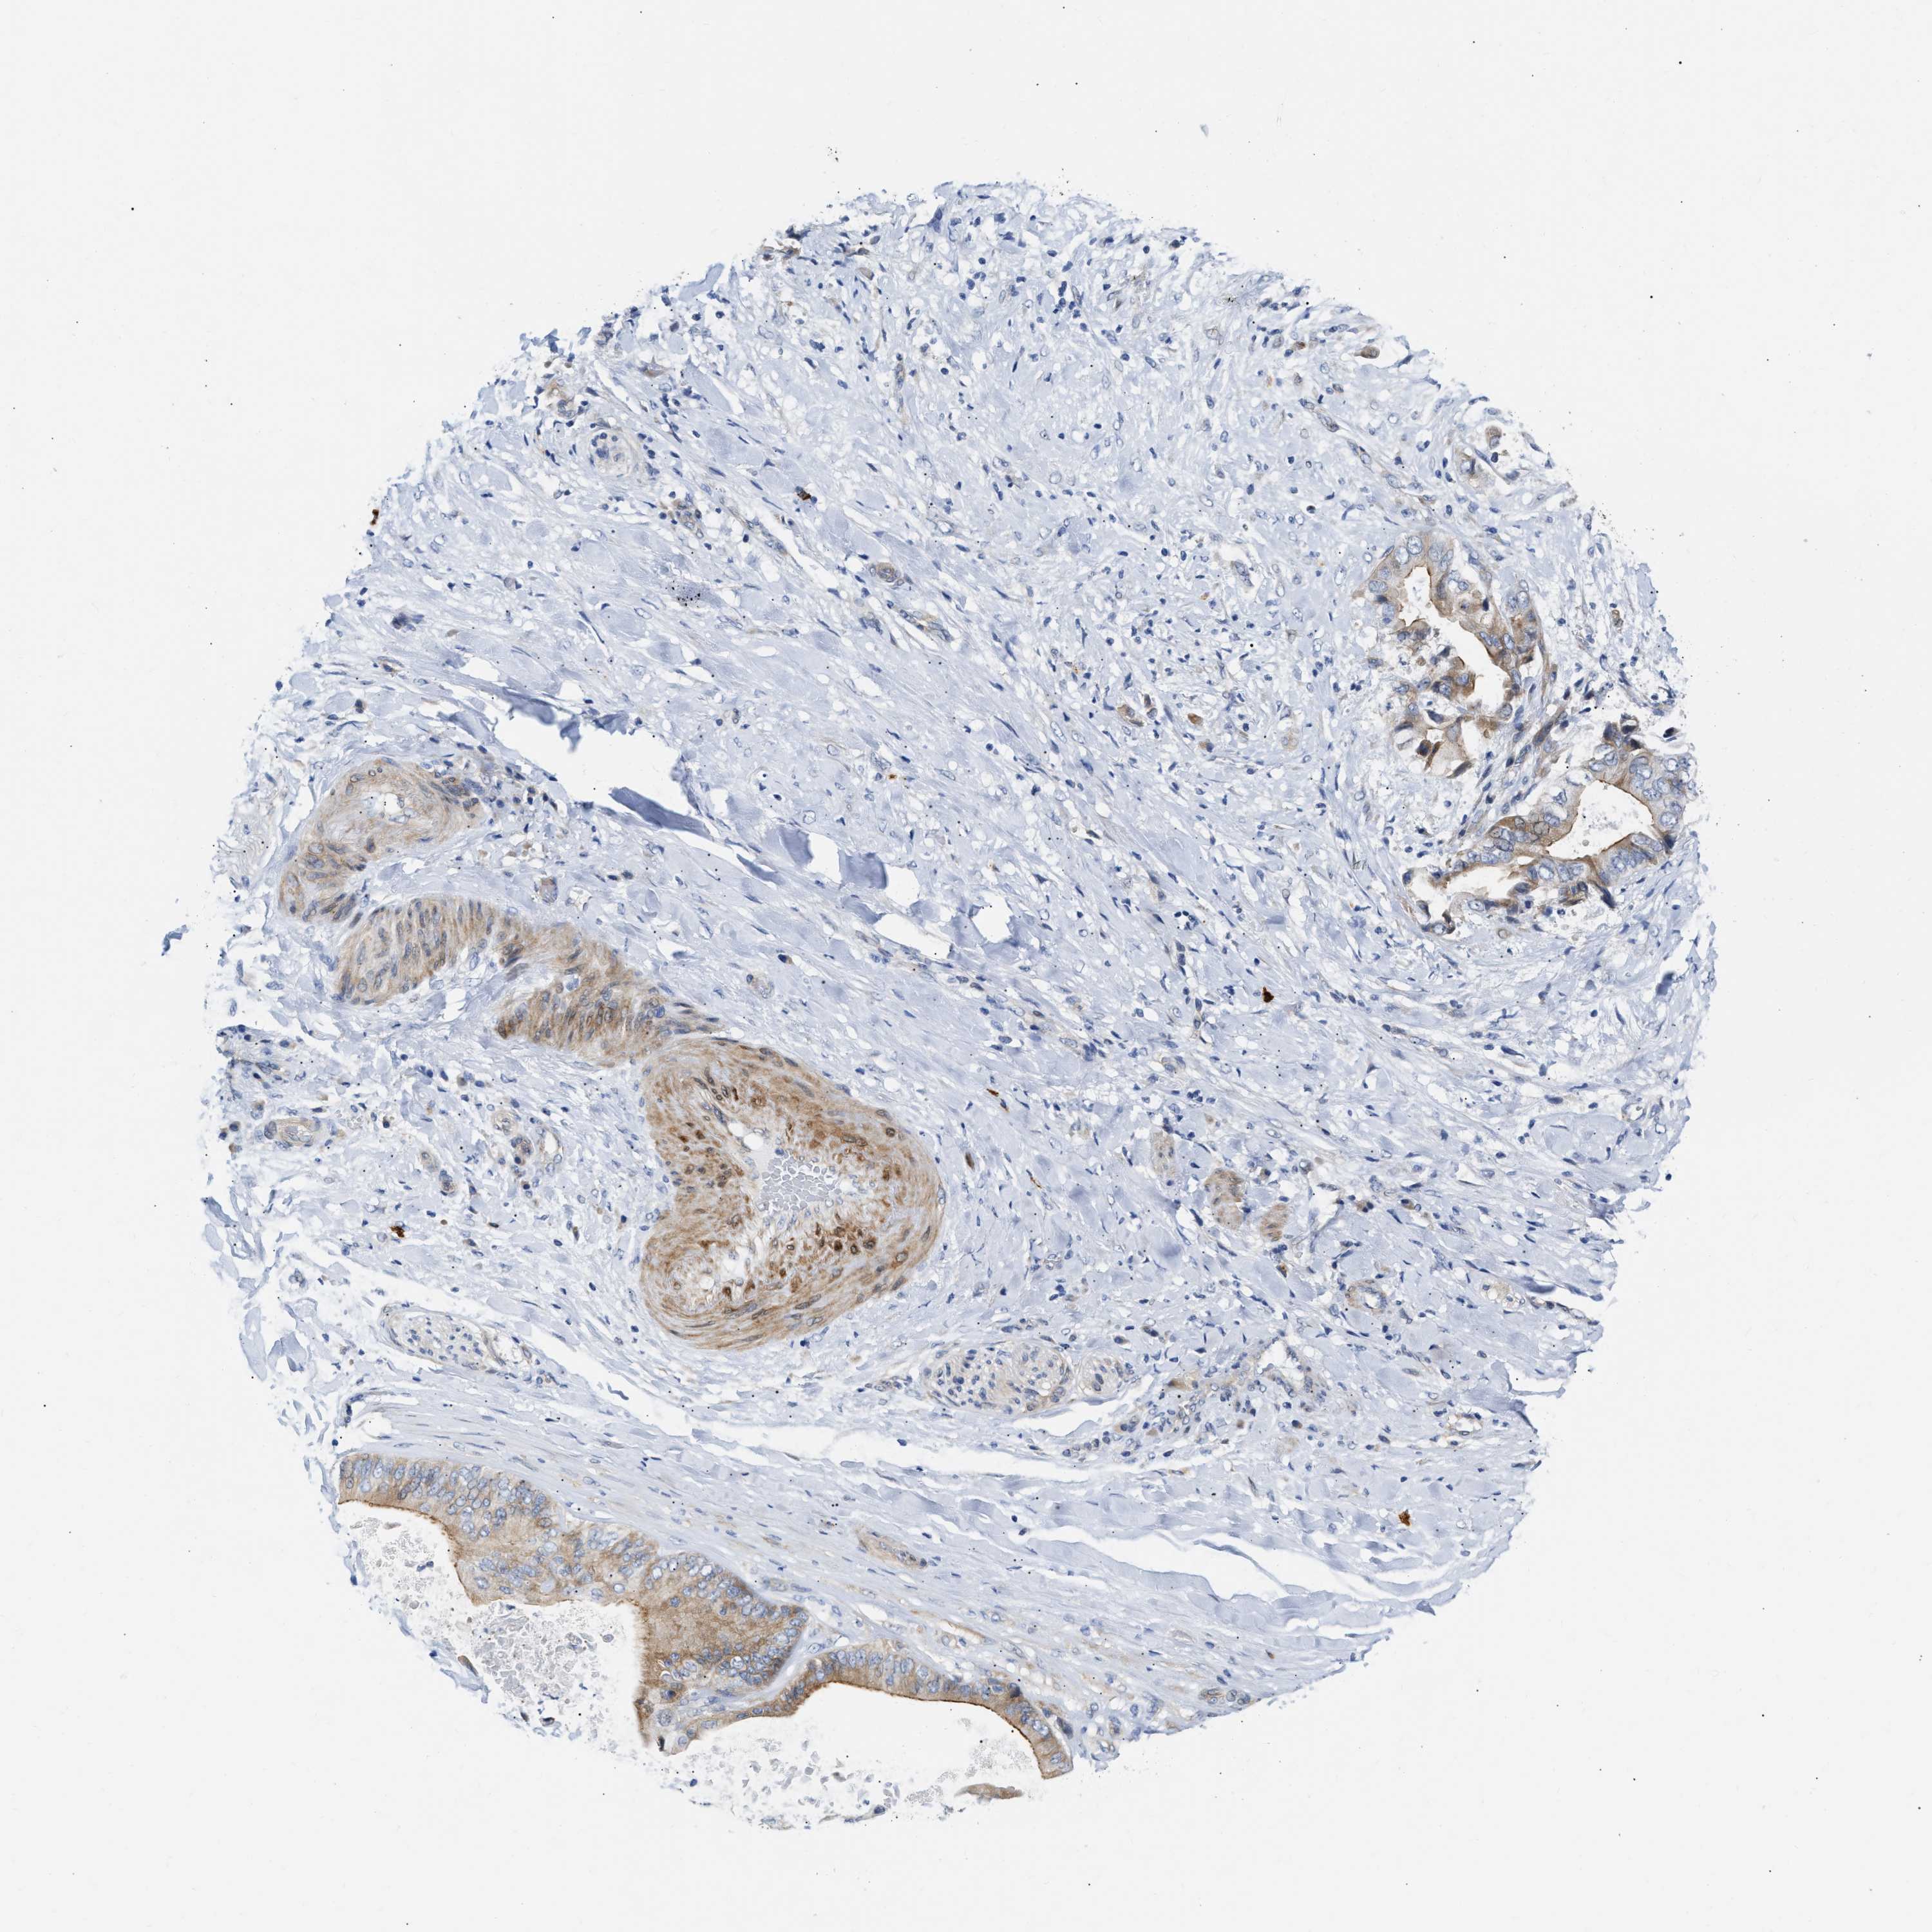

LIVER CANCER - Protein expressioni

A mouse-over function shows sample information and annotation data. Click on an image to view it in a full screen mode. Samples can be filtered based on level of antibody staining by selecting one or several of the following categories: high, medium, low and not detected. The assay and annotation is described here.

Note that samples used for immunohistochemistry by the Human Protein Atlas do not correspond to samples in the TCGA dataset.

Antibody stainingi

Antibody staining in the annotated cell types in the current human tissue is reported as not detected, low, medium, or high, based on conventional immunohistochemistry profiling in selected tissues. This score is based on the combination of the staining intensity and fraction of stained cells.

Each image is clickable and will lead to virtual microscopy that enables deeper exploration of all samples and also displays staining intensity scores, fraction scores and subcellular localization as well as patient and tissue information for each sample.

Antibody HPA001040

Antibody HPA001391

Antibody CAB020817

Staining

High

Medium

Low

Not detected

Intensity

Strong

Moderate

Weak

Negative

Quantity

>75%

75%-25%

<25%

None

Location

Nuclear

Cytoplasmic/membranous

Cytoplasmic/membranous,nuclear

Carcinoma, Hepatocellular, NOS

Cholangiocarcinoma